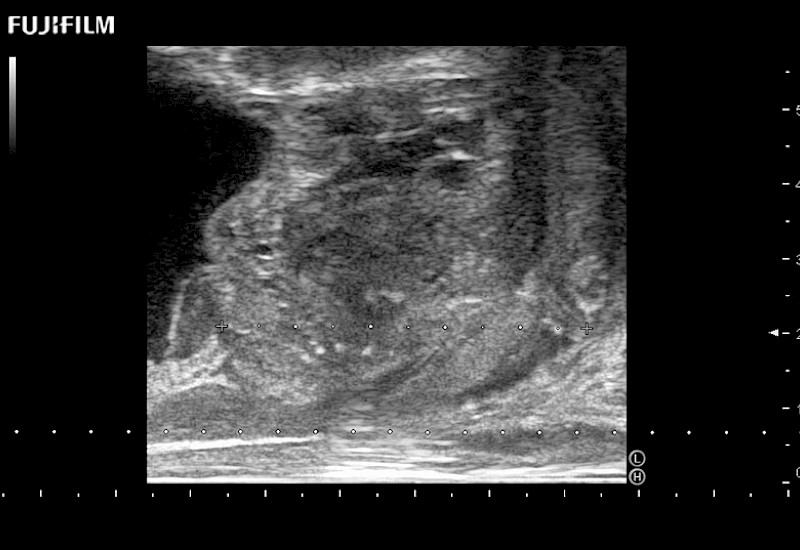

Abdominal transducer for biopsy, bladder and renal applications.